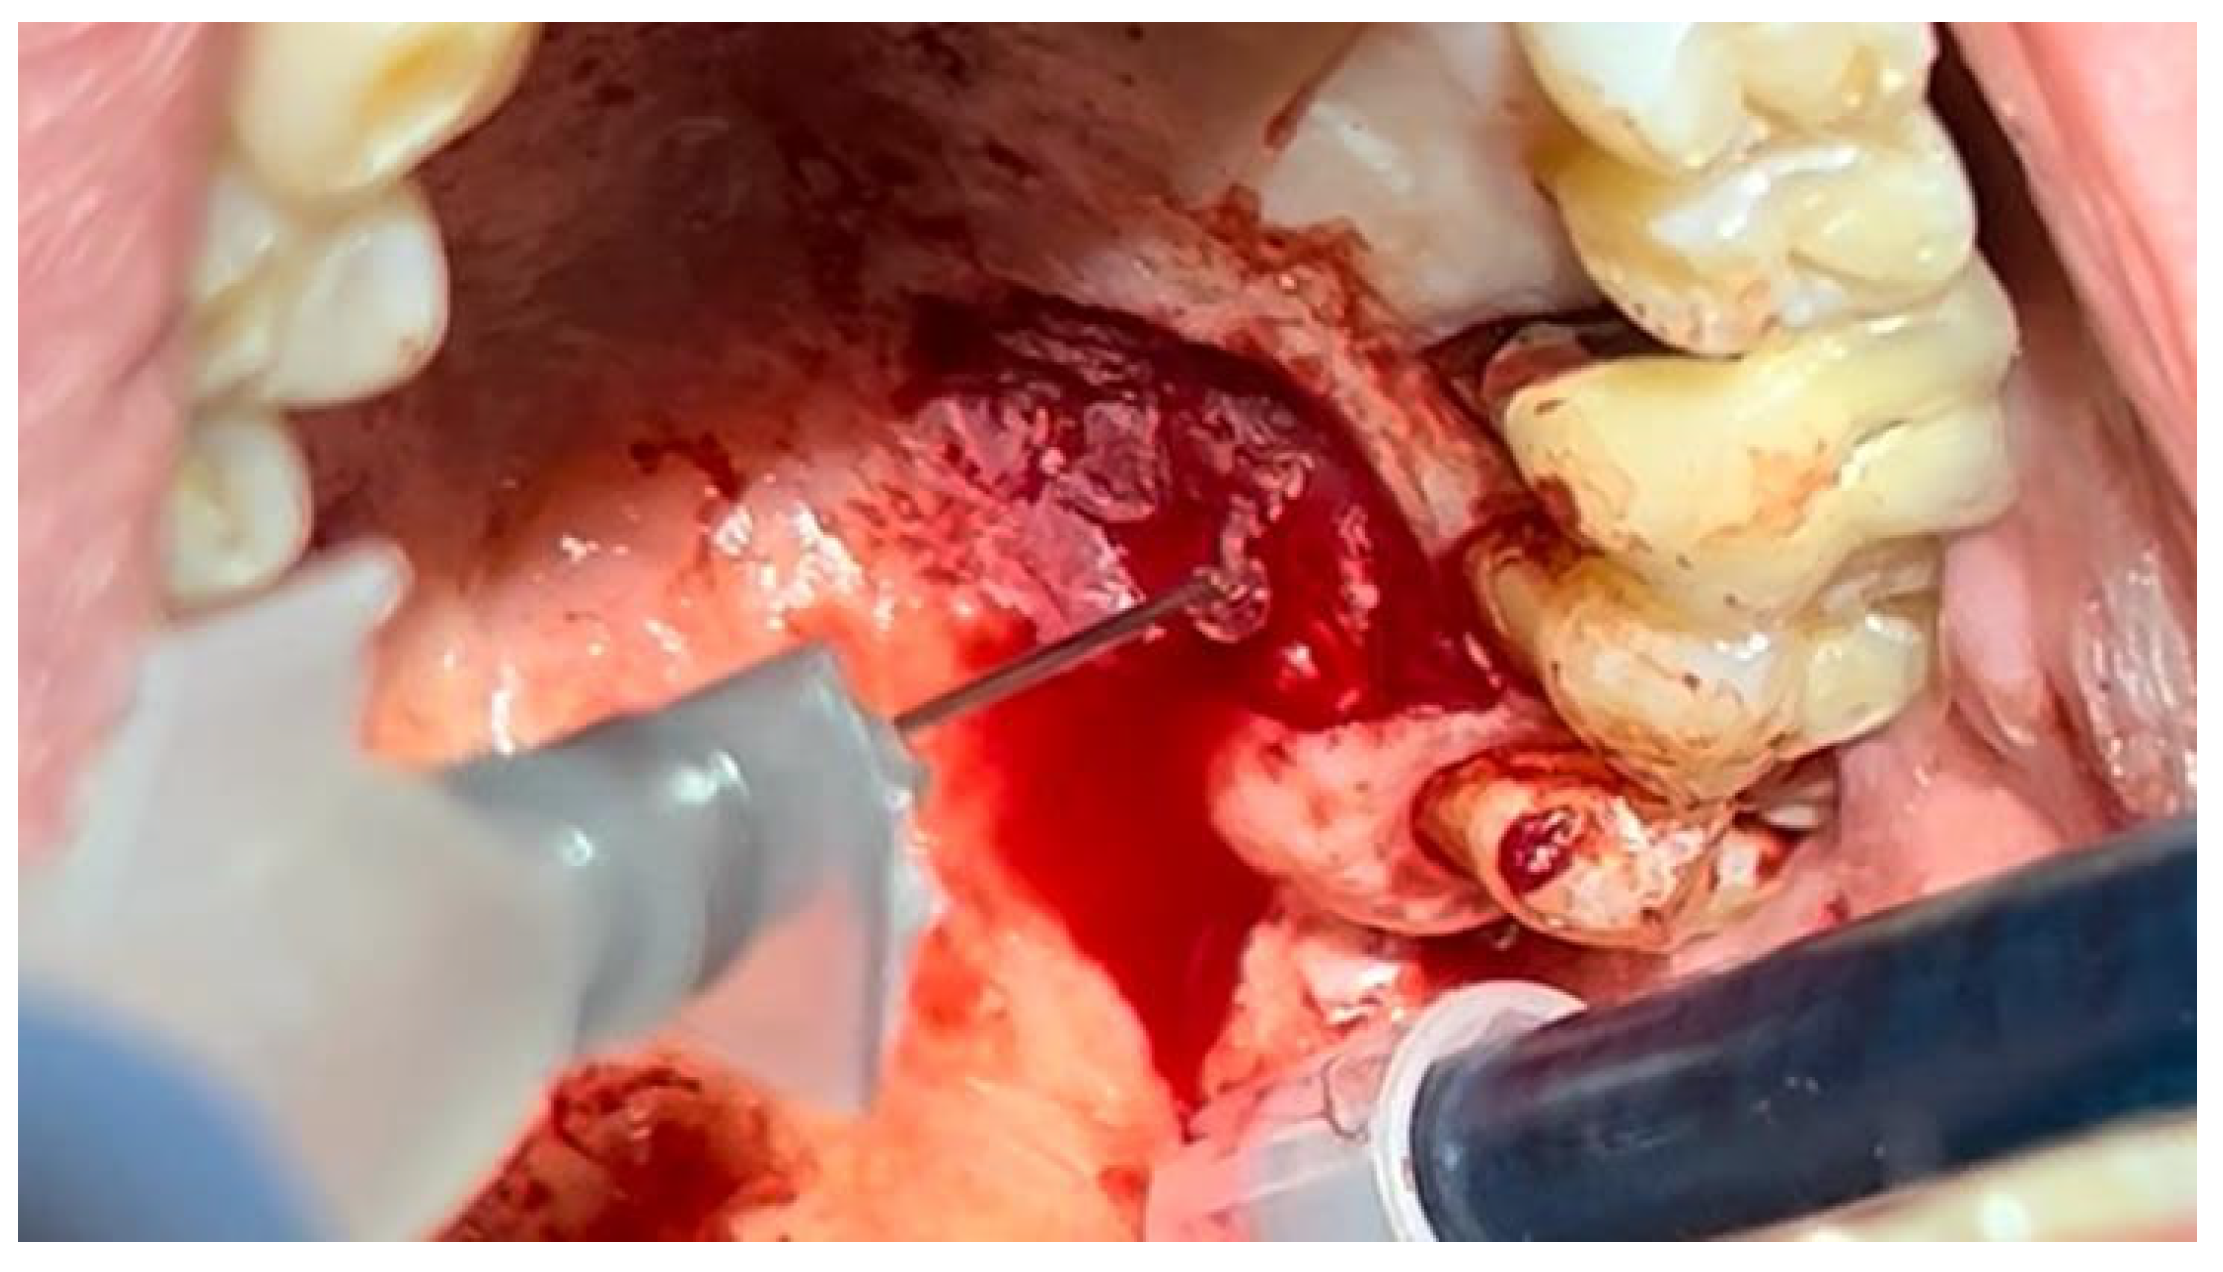

A similar technique was used in a 45-year-old patient with controlled hypertension, treated for the extraction of tooth 1.6 (Figure 11) and subsequent post-extraction implant-prosthetic rehabilitation (Figure 12). The surgical site was treated with bone graft material (Bio-Oss®—Geistlich), and a small amount of Glubran II was applied (Figure 13). Once again, Glubran II proved to be highly effective in stabilizing the graft material at the surgical site, providing excellent hemostasis and strong mechanical resistance from the film formed after polymerization (Figure 14).

Figure 11. Surgical extraction of 1.6.

Materials 18 02642 g011

Figure 12. Implant-prosthetic rehabilitation at the surgical site 1.6.